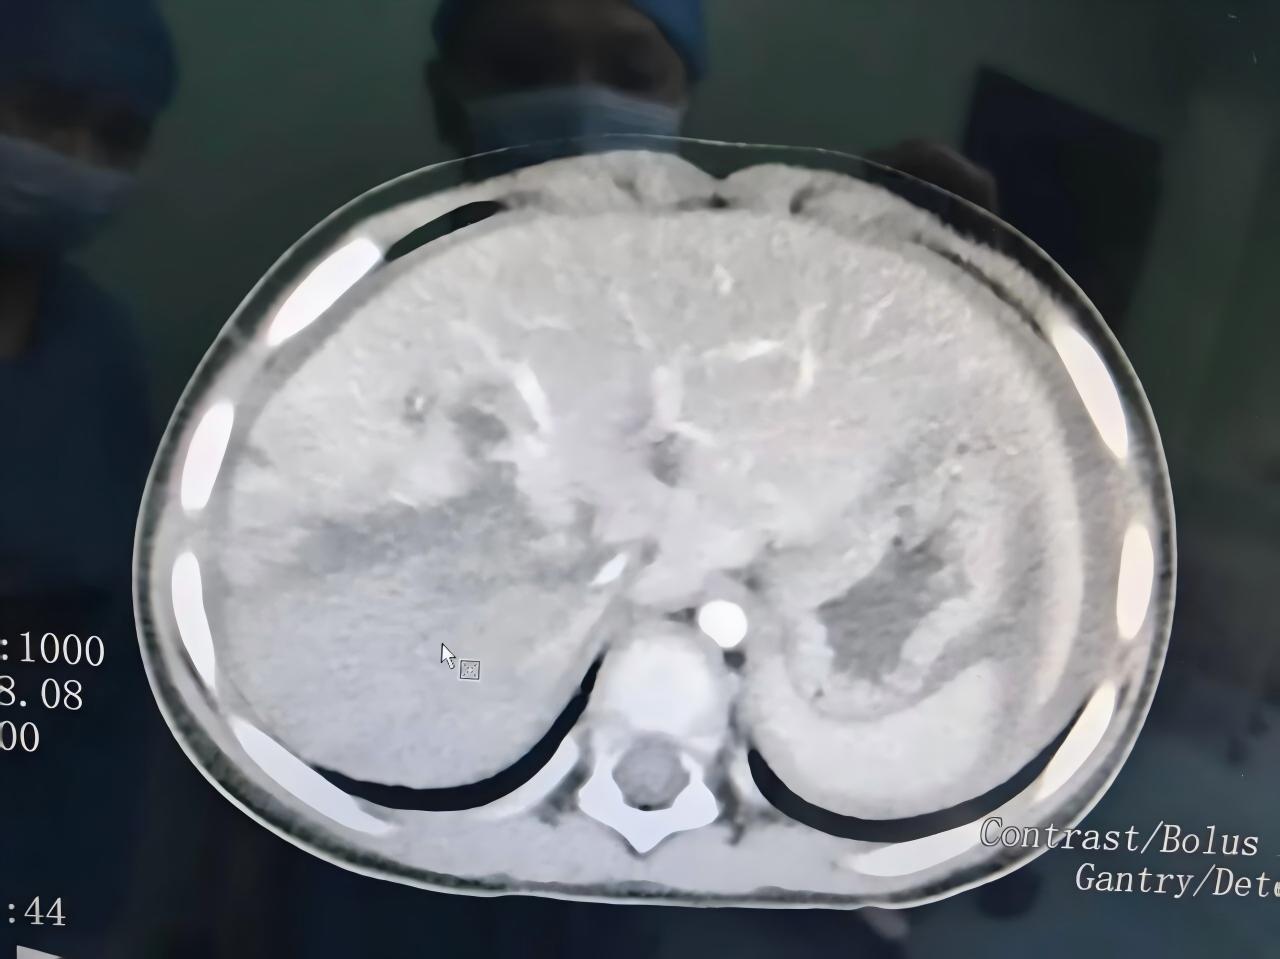

当急救团队赶到手术室时,情形比他们预料的还要危急。患儿心率急剧下降,血压极度不稳,血色素低至3克,尿量全无,已经陷入休克状态。术前CT显示,患儿的肝脏右后叶完全毁损,血肿扩展,从第一肝门一直裂伤至第二肝门,无法修复。